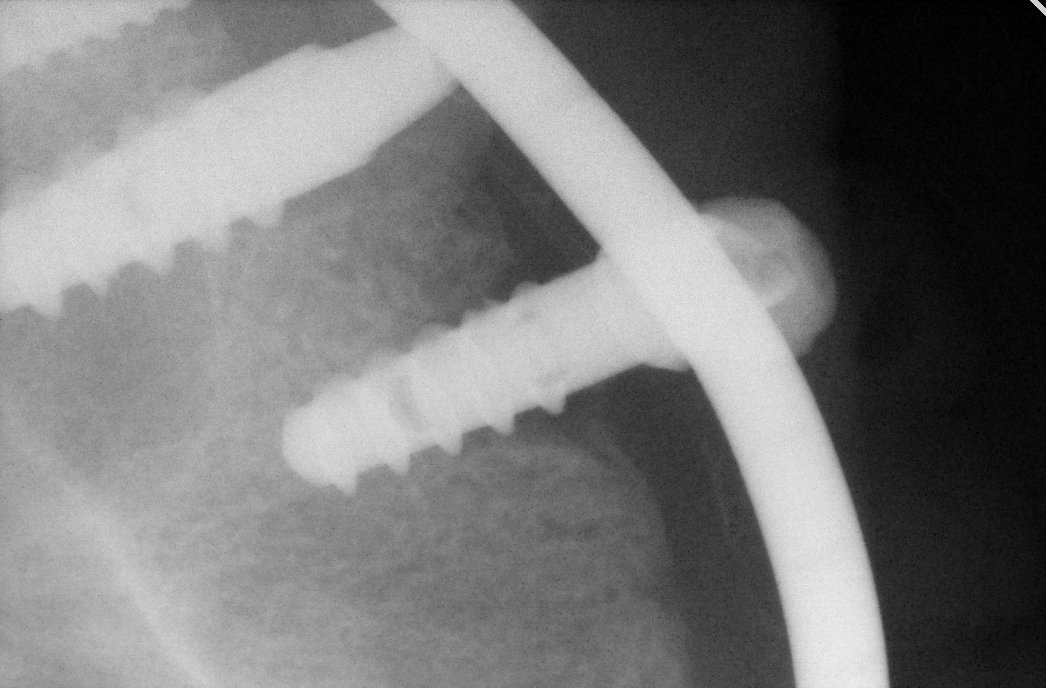

Hola buenos dias chicos, necesito que me ayudeis a saber que marca es este implante y la conexión, muchas gracias y un saludo. Os adjunto Rx Periapical

Buenos días, Si me podría ayudar con mi duda y detectar que implante es.

buenos días Hola por favor quisiera ayuda con la marca y medida de este implante . Gracias